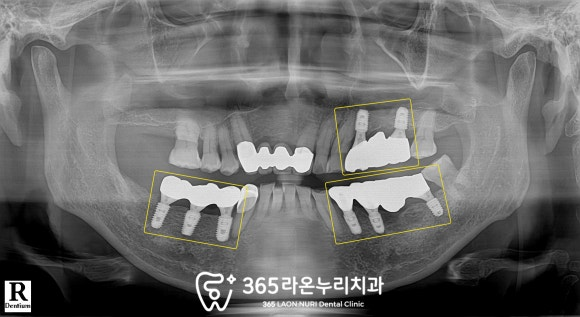

■ 6. 최종 보철

임플란트를 식립했던 부위마다

최종 보철까지 올라가고 난 모습입니다.

왼쪽 위 뼈가 많이 없으셔서

상악동 거상 및 골이식을 진행해 드렸는데

그 부위도 잘 결합되어서

빠른 기간에 잘 마무리가 되었습니다.